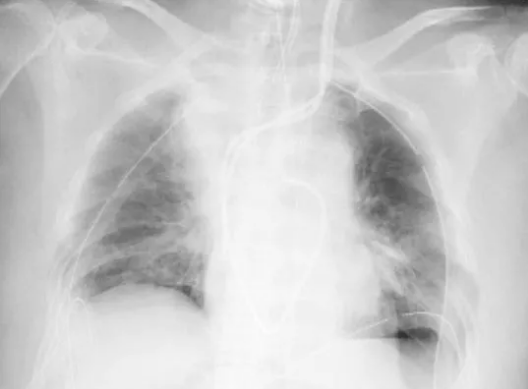

患者接受手术后的肺部情况。图片来源:京都大学医院

日本京都大学医院当地时间4月8日称,该院为一位已持续治疗约3个月的新冠肺炎患者移植了由家属提供的部分肺器官。这是全球首例针对新冠肺炎患者的活体肺移植。 据京都大学医院介绍,接受肺移植的是一位居住在关西的女性患者。该患者去年年底感染新冠病毒,呼吸状态恶化,于关西的一家医院就医,治愈后核酸检查结果为阴性,但由于后遗症,其双肺都萎缩变硬,没有恢复的希望,需要体外膜肺氧合(ECMO)维持肺机能。手术结束后,患者除肺部以外,其他脏器均无损伤,意识清醒。 因家属提出器官捐献申请,该患者于本月5日转院到京都大学医院。4月7日,医院将其丈夫和儿子捐献的一部分肺器官移植给该患者。患者目前在重症监护室,预计2个月后可出院,3个月后能回归正常社会生活,其丈夫和儿子目前情况良好。(央视新闻)